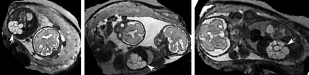

During image acquisition the fetus is not sedated and moves freely as well as the mother breathes normally. As a result, movements are likely to corrupt the scans, hiding pathology and causing overlap between different anatomical regions. In order to limit these artifacts, fast scanning sequences such as ssFSE [10] allow for the rapid acquisition of single slices at high in-plane resolution in a large field of view and good tissue contrast of the uterus. However, when acquiring a 3D volume through a stack of slices, inter-slice artifacts in the out-of-plane views are highly likely. Consequently, this restricts reliable diagnostics to individual slices in the current clinical practice. Fig. 1 depicts a typical example of motion related artifacts in a fetal single-shot fast spin echo (ssFSE) scan. The observed motion (c.f. Fig. 1 b & c) is of unpredictable nature and consists of a combination of maternal respiration movements, fetal movements and bowel movements.

Reconstruction of Fetal Organs: Exemplary PVR and SVR reconstructions under motion introduced by kicking of the fetus are shown in Fig. 11. PVR reconstruction results show an improved visual appearance and less blurring in the region with severe motion artifacts (arrow). An example of a challenging clinical case with a kidney malformation in one of twin fetuses, is shown in Fig. 8. Our clinical partners confirmed that such complications are easier to examine and to quantify after PVR-based reconstruction.

(a) Input

(b) SVR

(c) PVR